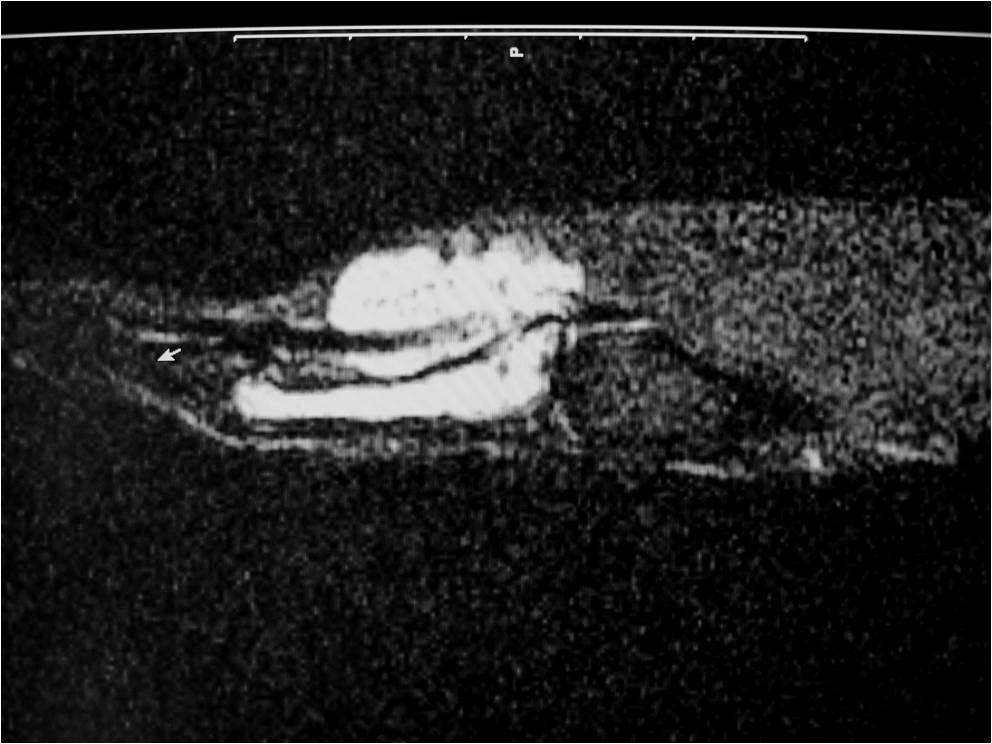

RADIOGRAPHIC PRESENTATION

Plain x-ray

• Soft tissue mass

• Pressure erosions in underlying bone in 15% of cases

• Calcifications are uncommon

MRI

• Isointense to muscle T1

• Low to intermediate T2

• May bloom on gradient echo (hemosiderin deposition)

• May demonstrate intense enhancement

Fig. 2-5: MR images of the hand with a giant cell tumor of tendon sheath shows a mass isointense to muscle on T1W and intermediate to high signal on T2W images. The lesion does not infiltrate the bone.